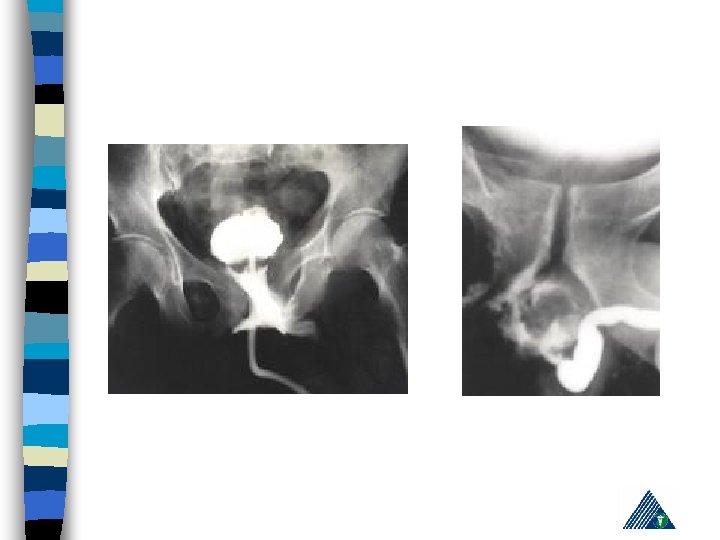

Bladder & Urethra – – – – Suspect trauma in the presence of: Blood at the urethral meatus DRE: “prostate displaced superiorly " Hematuria Penetrating abdominal, pelvic or genital injury Anterior pelvic fracture Open pelvic fracture Perineal laseration

Urethral Injury n A partial rupture could be a complete rupture during catheterisation! n A urethrogram should be performed n In the presence of urethral disruption, a suprapubic catheter should be placed.